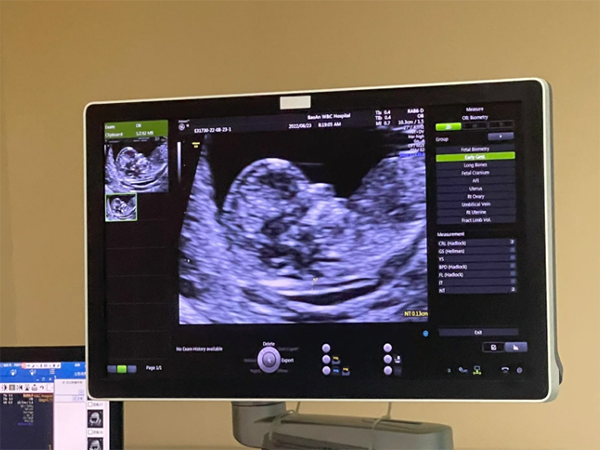

懷孕12周做nt是測量胎兒頸項透明層厚度,可用於判斷胎兒的生長情況,篩查由於染色體異常導致的嚴重胎兒畸形,胎停也就是指妊娠早期由於某種原因導致的胚胎髮育停止,引起胎兒死亡,多發生在妊娠12周以內,屬於婦產科常見的疾病,如果在做nt時發現胎停育的話,需要及時清宮,以免出現不良後果。

懷孕期間要選擇合適的時間進行各項產檢,不僅需要進行nt檢查,同時還需進行唐氏篩查和定期的超聲檢查,監測胎兒的生長髮育情況,如果檢查發現胎停,也不必過於焦慮,調整好心態,積極配合醫生進行相應染色體檢查,明確胎停育的原因,為下一次懷孕做準備。